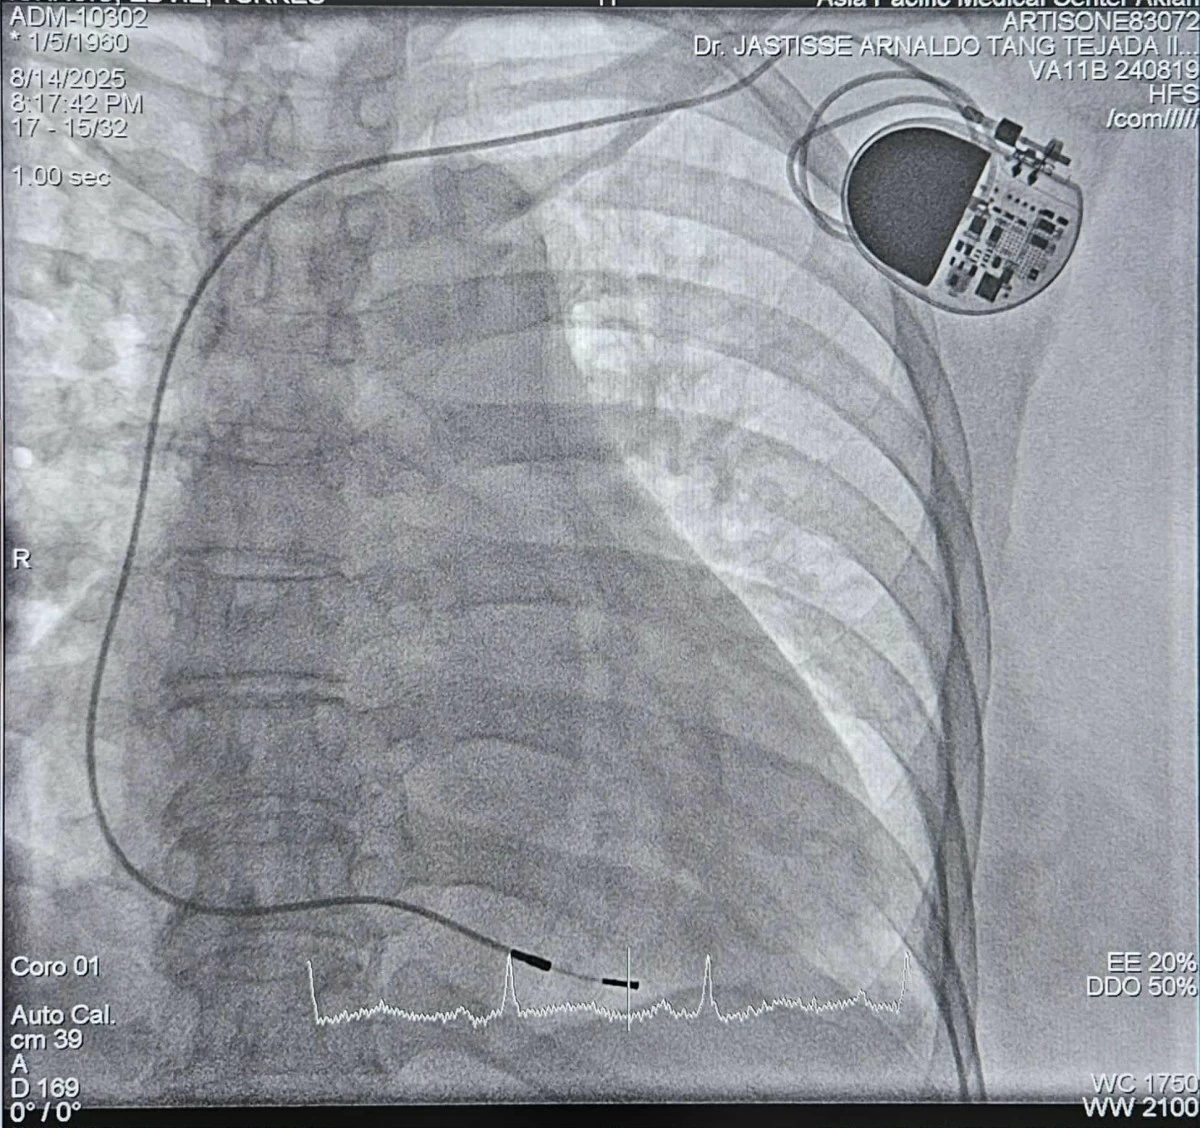

Western Visayas marked yet another achievement in the field of advanced and minimally invasive surgery, as a team of Aklan-based doctors has successfully implanted the first leadless pacemaker in the region using the Micra, considered the world's smallest pacemaker.

The team of doctors from the Asia Pacific Medical Center-Aklan --- headed by Dr. Claire B. Perez (Adult Cardiologist) as the attending physician and Interventional cardiologist, Dr. Jastisse Arnaldo T. Tejada III (Asia Pacific Medical Center-Aklan & Perpetual Help Medical Center-Las Pinas), Dr. Douglas Bailon (St. Luke's Medical Center-BGC), anesthesiologist Dr. Francis Stemar B. Villaruel, and endocrinologist Dr. Gregory Joseph Ryan Ardena --- implanted the device on a 69-year-old male diagnosed with sick sinus syndrome, a heart condition where the sinoatrial node doesn't function properly, leading to abnormal heart rhythms and symptoms like dizziness, syncope or loss of consciousness.

Roughly the size of a large vitamin capsule, the Micra is almost invisible once in place, giving patients the benefit of advanced technology without the visible signs and complications of surgery. Unlike the conventional pacemakers that require a surgical "pocket" in the chest and wires connected to the heart, the breakthrough device is implanted directly inside the heart through a small entry into the vein in the leg. This minimally invasive procedure allows patients to recover faster and have a lower risk of infections. Aesthetically, it leaves no visible surgical scar compared to traditional pacemaker implants.